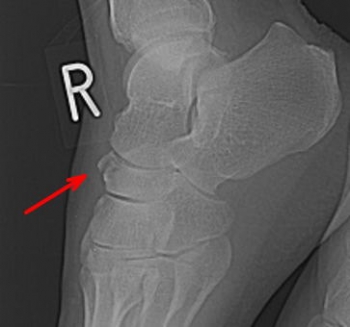

½®¾õ¹ü¹üÀÞ

½®¾õ¹ü¹üÀÞ¤ÎʬÎà

­¡½®¾õ¹üÂÎÉô¹üÀÞ

­¢½®¾õ¹üÁÆÌ̹üÀÞ

½®¾õ¹ü¹üÀÞ¤ÎȯÀ¸µ¡½ø

²ðã³°ÎϤˤè¤ë¤Ë¤è¤ëȯÀ¸ÉÑÅÙ¤¬¹â¤¤¡£

¹üÂÎÉô¤Î¹üÀޤϹâ½ê¤è¤êÄÆÍ¤ÆÂ­Éô¥¢¡¼¥Á¤¬°µÊ¿¤µ¤ì¡¢¥¢¡¼¥Á¤ÎºÇ¹âÉô¤Ë¤¢¤ë½®¾õ¹ü¤¬µ÷¹ü¹üƬ¤ÈµÊ¾õ¹ü¤Ë¤è¤Ã¤Æ¶¯¤¯°µÇ÷¤µ¤ì¤Æ¹üÀÞ¤¹¤ë¡£

ÇØÂ¦¤Î¹üÊҤϞ°Ì¤·Ã¦±±¤¹¤ë¤³¤È¤¬Â¿¤¤¡£

½®¾õ¹üÁÆÌ̤ιüÀޤϡ¢Â­Éô¤Î³°Å¾¤Ë¤è¤ê¸åæú¹ü¶Ú¤Î¸£°úÎϤˤè¤ëÇíÎ¥¹üÀÞ¤òµ¯¤³¤¹¡£

ľã³°ÎϤˤè¤Ã¤Æ¡¢¾åÊý¤Þ¤¿¤Ï²¼ÆâÊý¤ÎÁÆÌ̤¬¹üÀÞ¤¹¤ë¤³¤È¤¬¤¢¤ë¡£